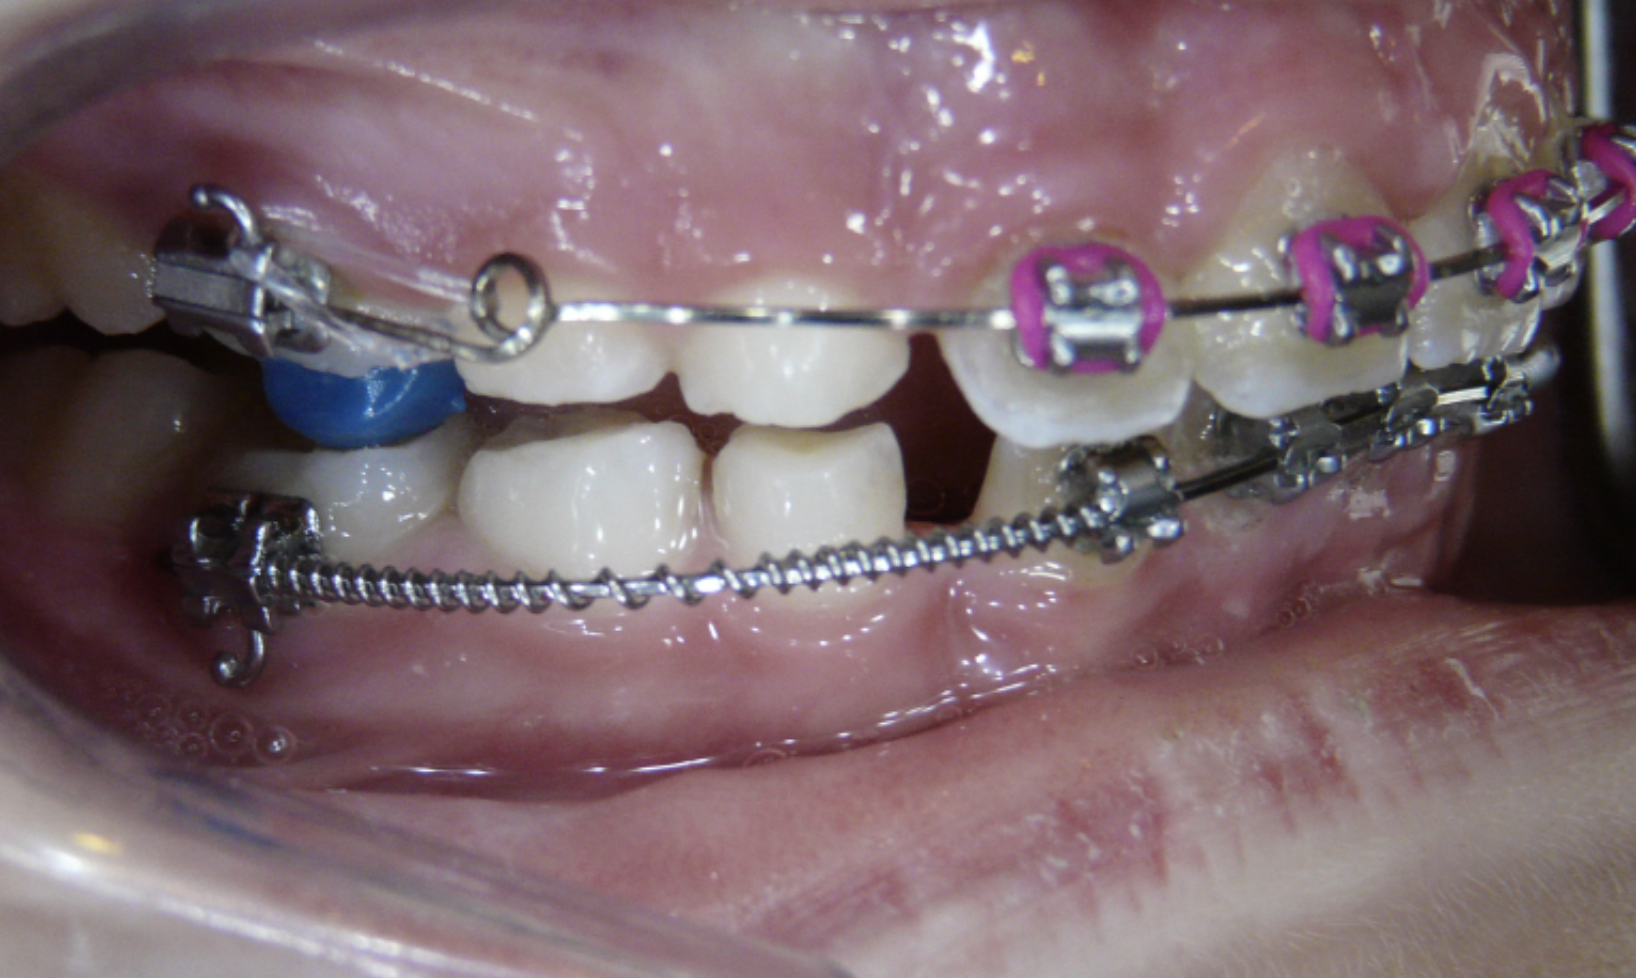

Ectopic Eruption

Ectopically erupting maxillary molar